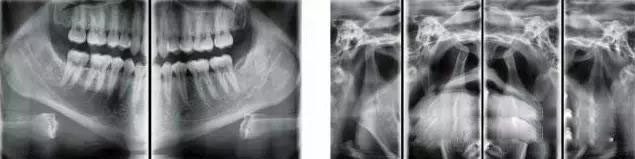

PaX-i 雙傳感器設備 |